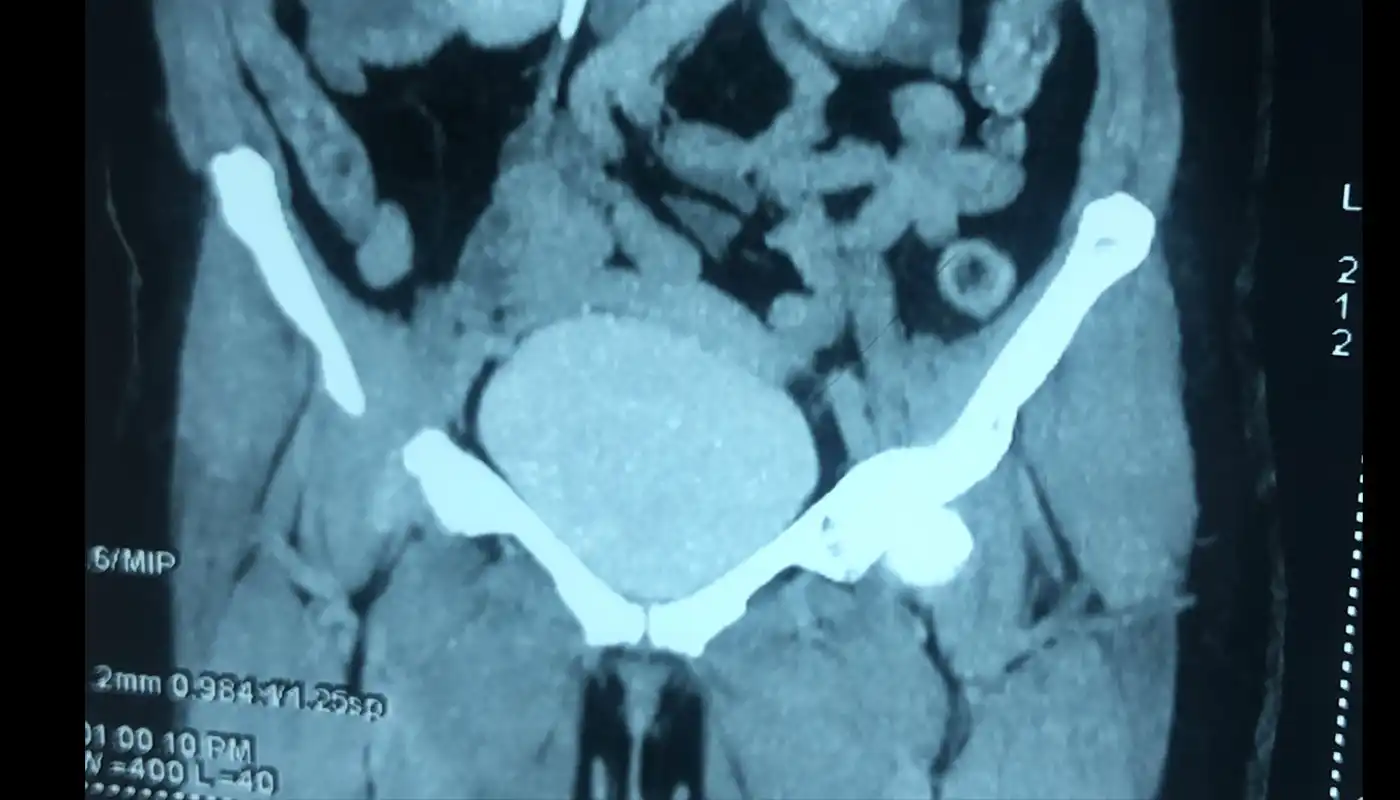

- Bladder Cancer: bladder cancer is 4th most common cancer in males and 8th most common cancer in females worldwide. Most common presentation is painless hematuria. It most commonly occurs in 6th decade of life. Smoking remains most important risk factor responsible for 48 to 74% of bladder . risk of bladder cancer due to smoking is dose and duration dependent. If detected in early stage most of the bladder cancers can be managed endoscopically without major surgery, however in muscle invasive stage urinary bladder needs to be removed for complete cure from cancer, further advance stages are treated with multidisciplinary approach using surgery , chemotherapy and immunotherapy.